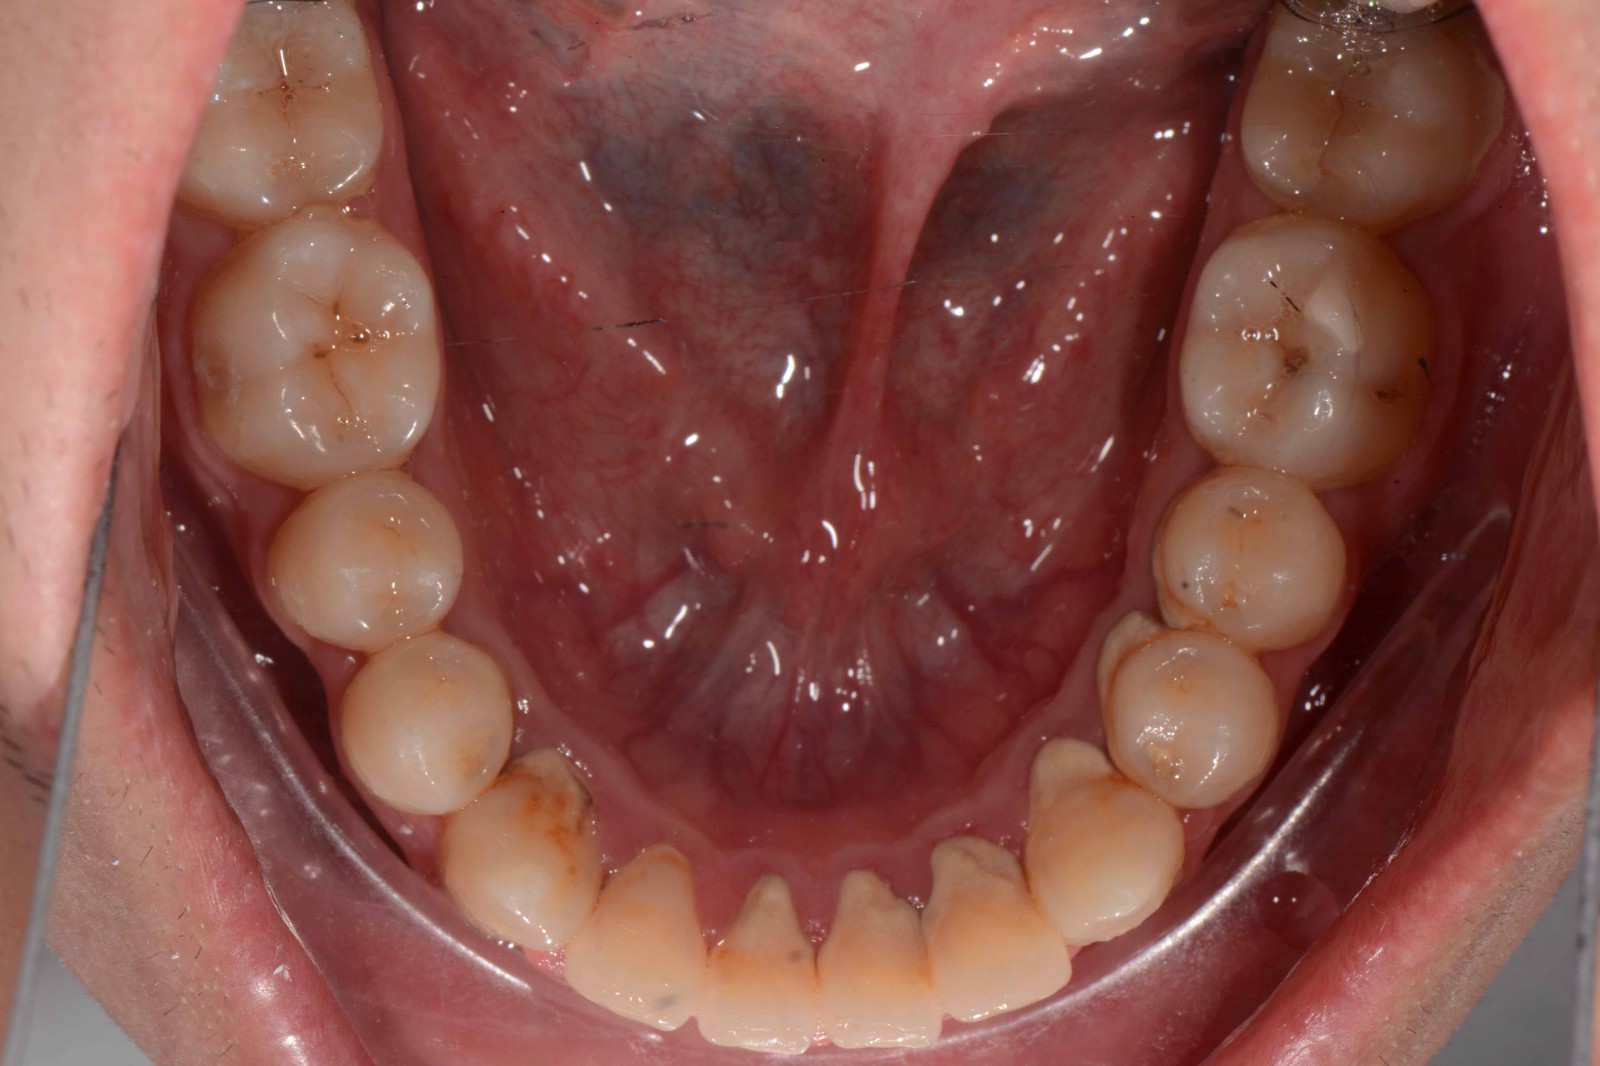

检查:拍摄口内面像照片,拍摄全景片侧位片,口扫,上下颌I-II度拥挤,中线不齐,局部反合,磨牙基本中性关系,上下前牙比较直立。

矫治后: